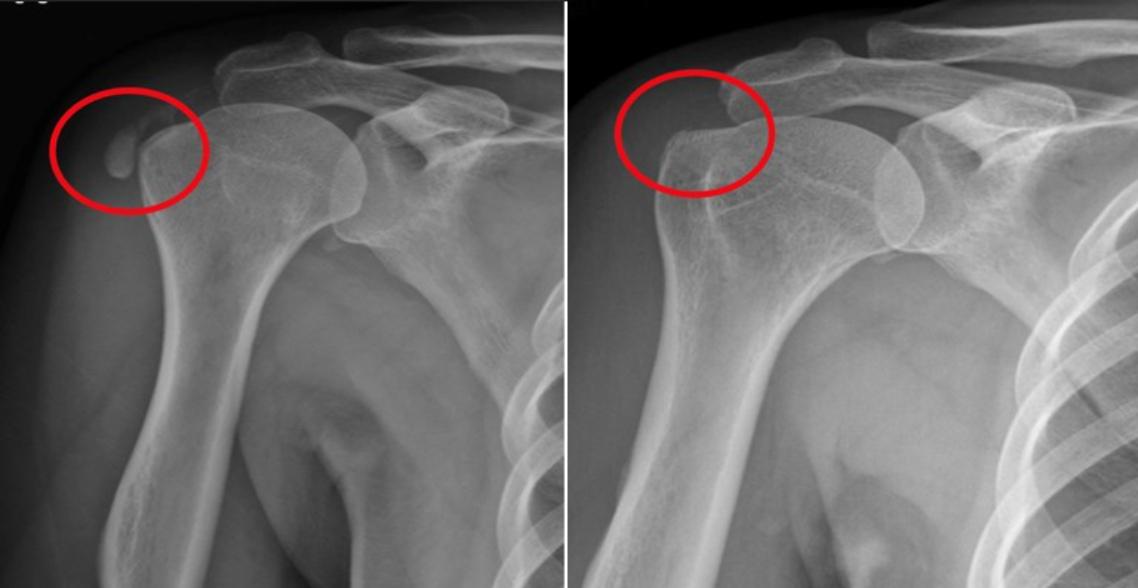

王小姐48歲,在一家貿易公司擔任行政主管。4個月前開始,她開始覺得右肩不適,一開始只是穿脫衣服時感覺卡卡的,後來連夜間睡覺翻身都會痛醒。她先到地方診所求醫,經X光與超音波檢查後診斷為肩旋轉肌腱鈣化性肌腱炎。

周文毅醫師指出,肩鈣化性肌腱炎是造成肩部疼痛的常見病症。根據國外研究,盛行率約為 2.5%至10%,若以台灣人口估算,約58.8萬至235萬人可能受影響。最常見的發生位置為旋轉肌群中的「棘上肌」,而旋轉肌是肩部力量、穩定度與活動度的重要結構。此疾病與退化、內分泌或代謝相關疾病有關,女性盛行率較高,常見於30至60歲之間的族群。雖然體外震波(ESWT)治療已被證實能有效改善此病症症狀,但臨床治療滿意度仍僅約6至7成。